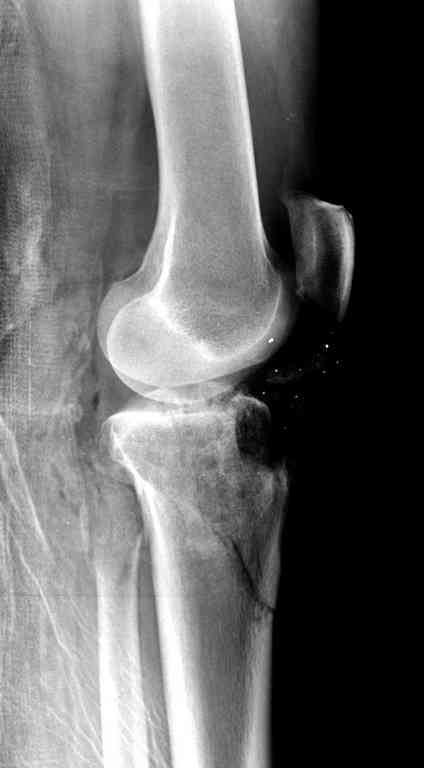

Поступила к нам пациентка 19 лет с диагнозом "Состояние после открытого многооскольчатого перелома дистального метаэпифиза правого бедра, проксимального метаэпифиза большеберцовой кости". Травма в июне 2010 года в Индии. ДТП.

Все ипсилатеральные переломы относятся к категории нестабильных, и лечение их бывает сложным из-за двойного перелома вокруг сустава (floating joint). Основная тактика состоит в проведении поэтапного лечения с окончательной фиксацией cуставной поверхности.

На первом этапе с задачей справляется наружный фиксатор, который создает благоприятные условия для закрытия ран и контролирует длину конечности. На данном этапе рекомендована КТ, чтобы увидеть топографию фрагментов для расчета направления фиксирующих элементов.

Состояние мягкотканого покрытия подскажет о готовности к окончательной фиксации. При дефектах кости придерживаются тактики максимального сохранения костной массы.

На вашем снимке из-за ротации трудно угадать положение пластины, и желательно сделать снимок с захватом верхнего участка бедра.

Одинокий кортикальный шуруп не удержит тибиальный бугор, сустав тибиал плато оставлен без репозиции и фиксации.

План с протезированием чересчур агрессивный, больная слишком молодая. В данный момент для удержания конструкции необходимо установить наружный фиксатор между бедром и голенью. Обработку продолжать с применением антибиотиков и вакуумирования.